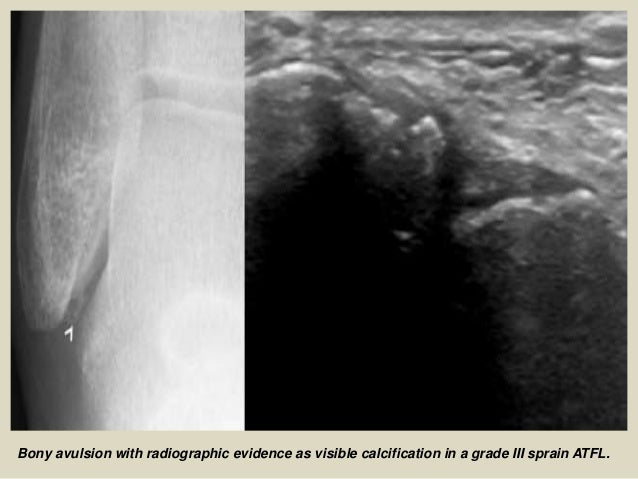

Bony avulsion with radiographic evidence as visible calcification in a grade III sprain ATFL.

70. 70. Bony avulsion with radiographic evidence as visible calcification in a grade III sprain ATFL.